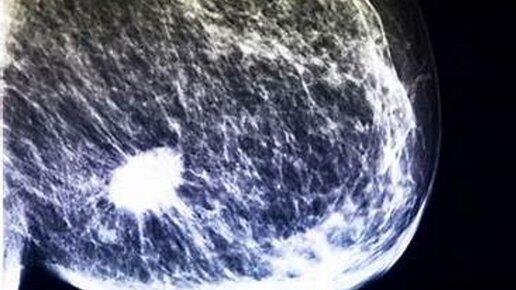

Что значит BI-RADS в заключении УЗИ, маммографии и МРТ молочных желез? Примеры.

⁃ BI-RADS - это международная шкала оценки результатов исследования молочных желез по степени риска наличия злокачественной опухоли. ⁃ шкала применима к любому инструментальному исследованию молочной железы: УЗИ, маммографии и МРТ. ⁃ в заключении после проведения исследования доктор обязательно должен указать категорию BI-RADS Интерпретация BI-RADS: ⁃ BI-RADS 0 - означает что данных недостаточно для оценки риска и необходимо повторное, либо дополнительное исследование. ⁃ BI-RADS 1 - норма, отсутствие узловой патологии...

BI-RADS - что это такое?

В заключении маммографии, УЗИ молочных желёз и МРТ молочных желёз часто мы можем видеть аббревиатуру "BI-RADS" (Bi-RADS, BIRADS, birads и т.п.). Что она означает? Давайте разберёмся. Существует 7 категорий BI-RADS от 0 до 6. Например, BIRADS 2 (иногда пишут римскими цифрами: BI-RADS II). Поговорим о каждой по отдельности. BI-RADS 0. Это значит, что обследование необходимо повторить, то есть на данный момент исследование не представляется возможным. В большинстве случаев из-за недостаточной визуализации...